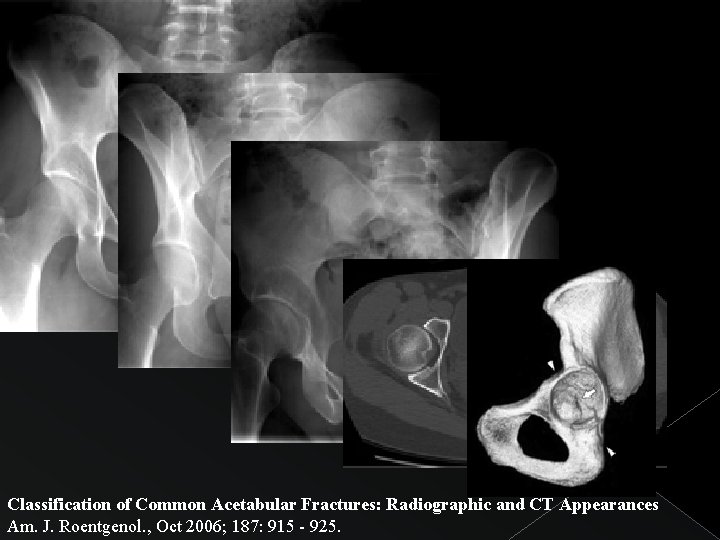

Classification of Common Acetabular Fractures: Radiographic and CT Appearances Am. J. Roentgenol. , Oct 2006; 187: 915 - 925.